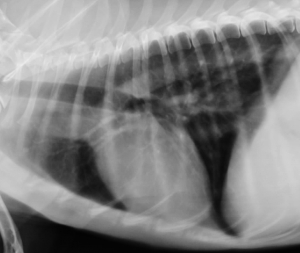

左下が胸部レントゲン写真で、寄生虫性の肺炎、気管支炎を示しております。写真のワンちゃんは生後1年弱、糞線虫が治療されていませんでした。右下の写真は正常レントゲン写真です。